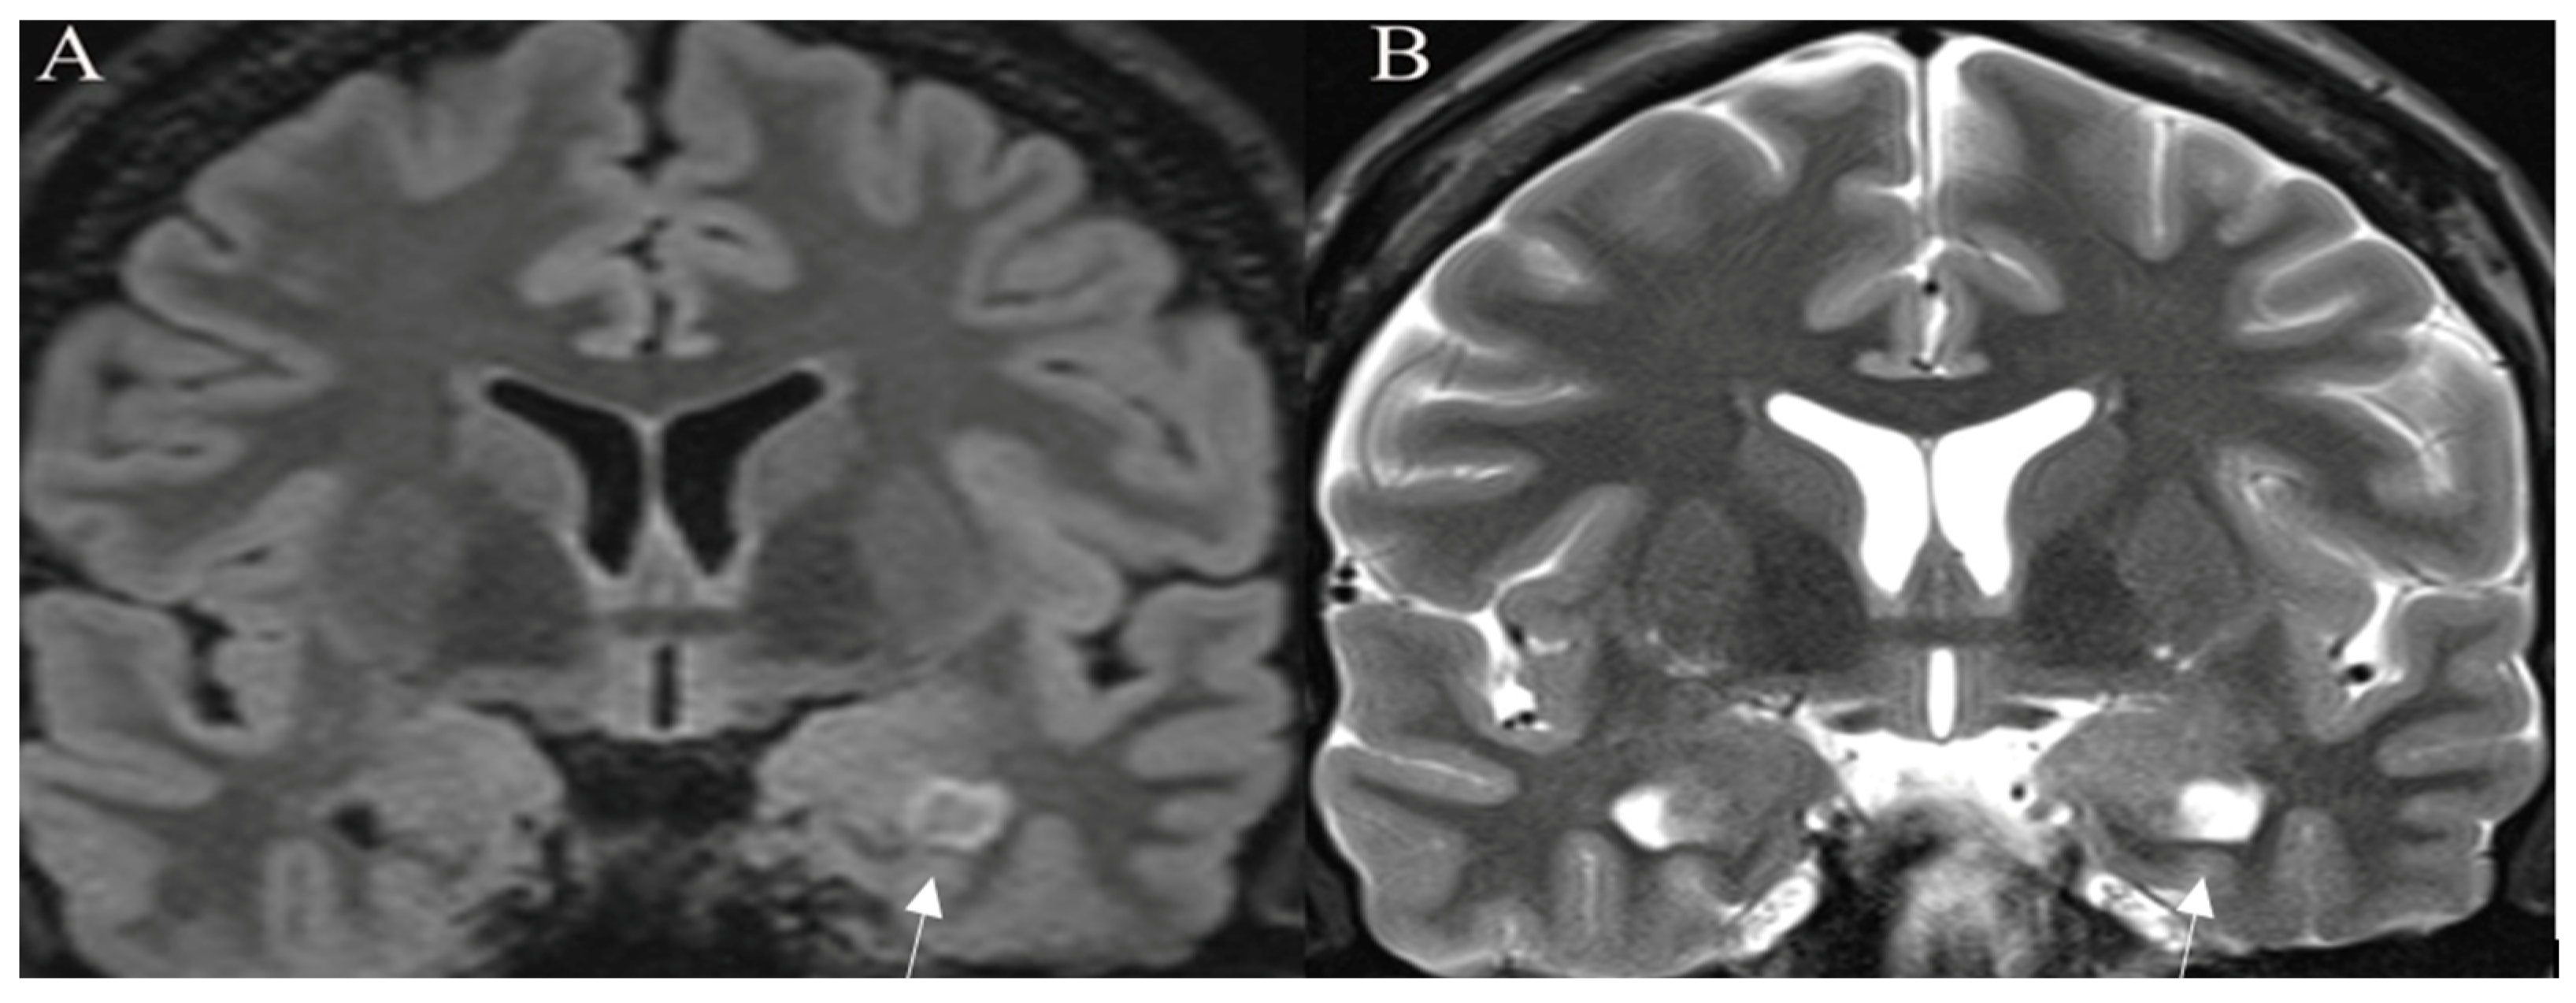

Standard Imaging Sequences

- Batchala, P.P.; Muttikkal, T.J.E.; Donahue, J.H.; Patrie, J.T.; Schiff, D.; Fadul, C.E.; Mrachek, E.K.; Lopes, M.B.; Jain, R.; Patel, S.H. Neuroimaging-Based Classification Algorithm for Predicting 1p/19q-Codeletion Status in IDH-Mutant Lower Grade Gliomas. AJNR Am. J. Neuroradiol. 2019, 40, 426–432. [Google Scholar] [CrossRef]